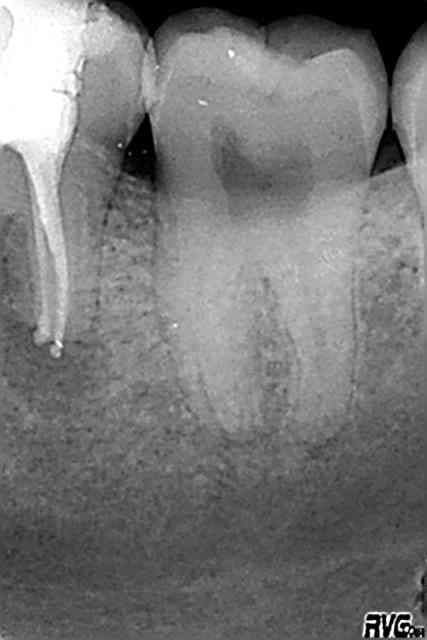

à moi, 26mm de bonheur (j'ai mis la digue mais pas de radio perop)

R2 qk1svf - Eugenol

Je suis étonné de la densité par contre, ça a bien poussé vers le haut pour un résultat pas si dense.

Allez j'en mets une autre, satisfaisante en densité

edit : tant que ya pas un mac spadden pété on est pas sur que c'est bien tassé :p